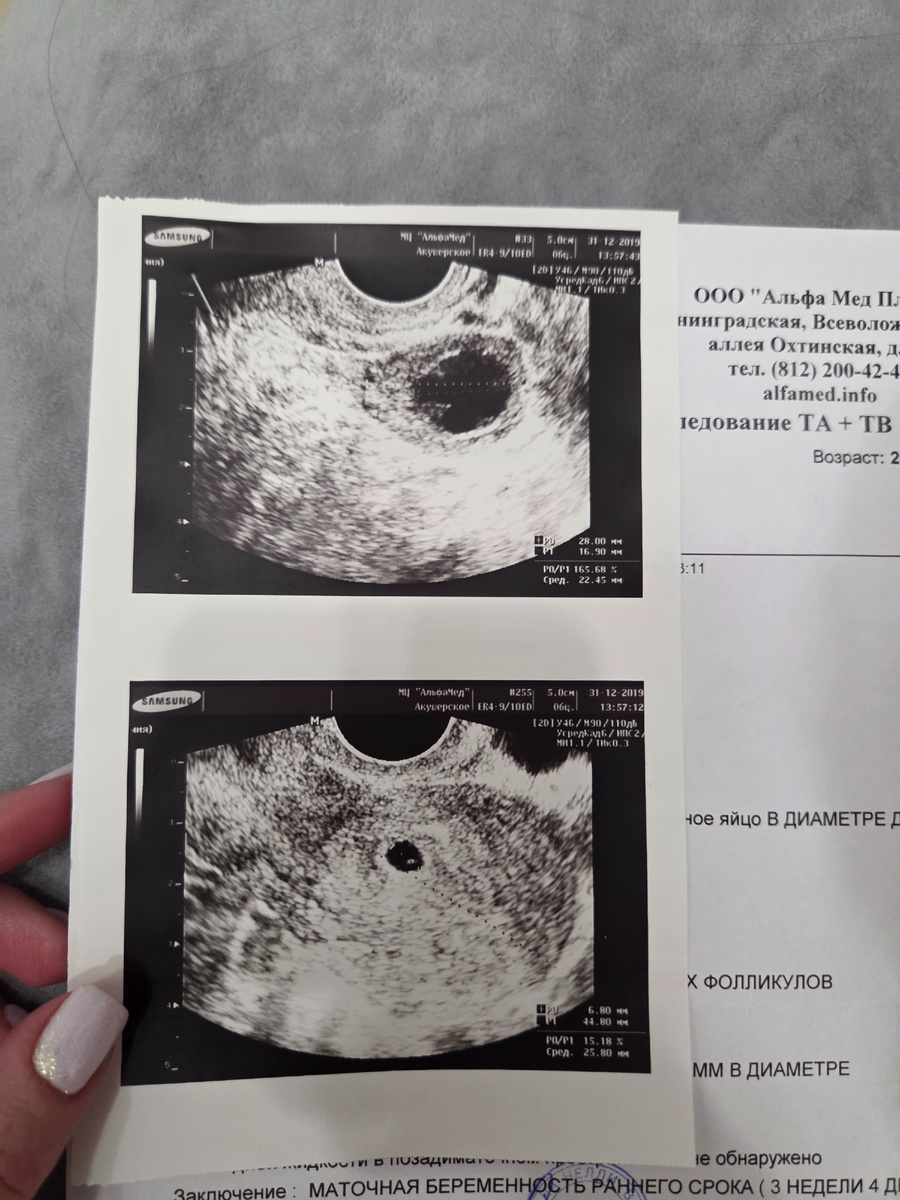

Именно в этот день я узнала, что впредь моя жизнь не будет прежний, ведь внутри меня зародилась новая жизнь - я беременна.

Я встречаю со снимком УЗИ, осознавая, что год мне предстоит очень непростой. Но тогда я и подумать не могла, что 2020 окажется сложным и для всего человечества.